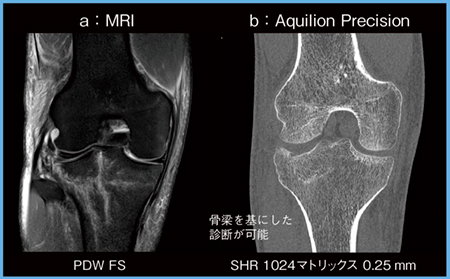

症例2は,22歳,男性,脛骨高原骨折である(図2)。MRI(図2 a)と比較して,Aquilion Precisionでは骨梁の異常が明瞭に描出されており(図2 b),骨梁を基にした診断にきわめて有用である。

図2 症例2:脛骨高原骨折